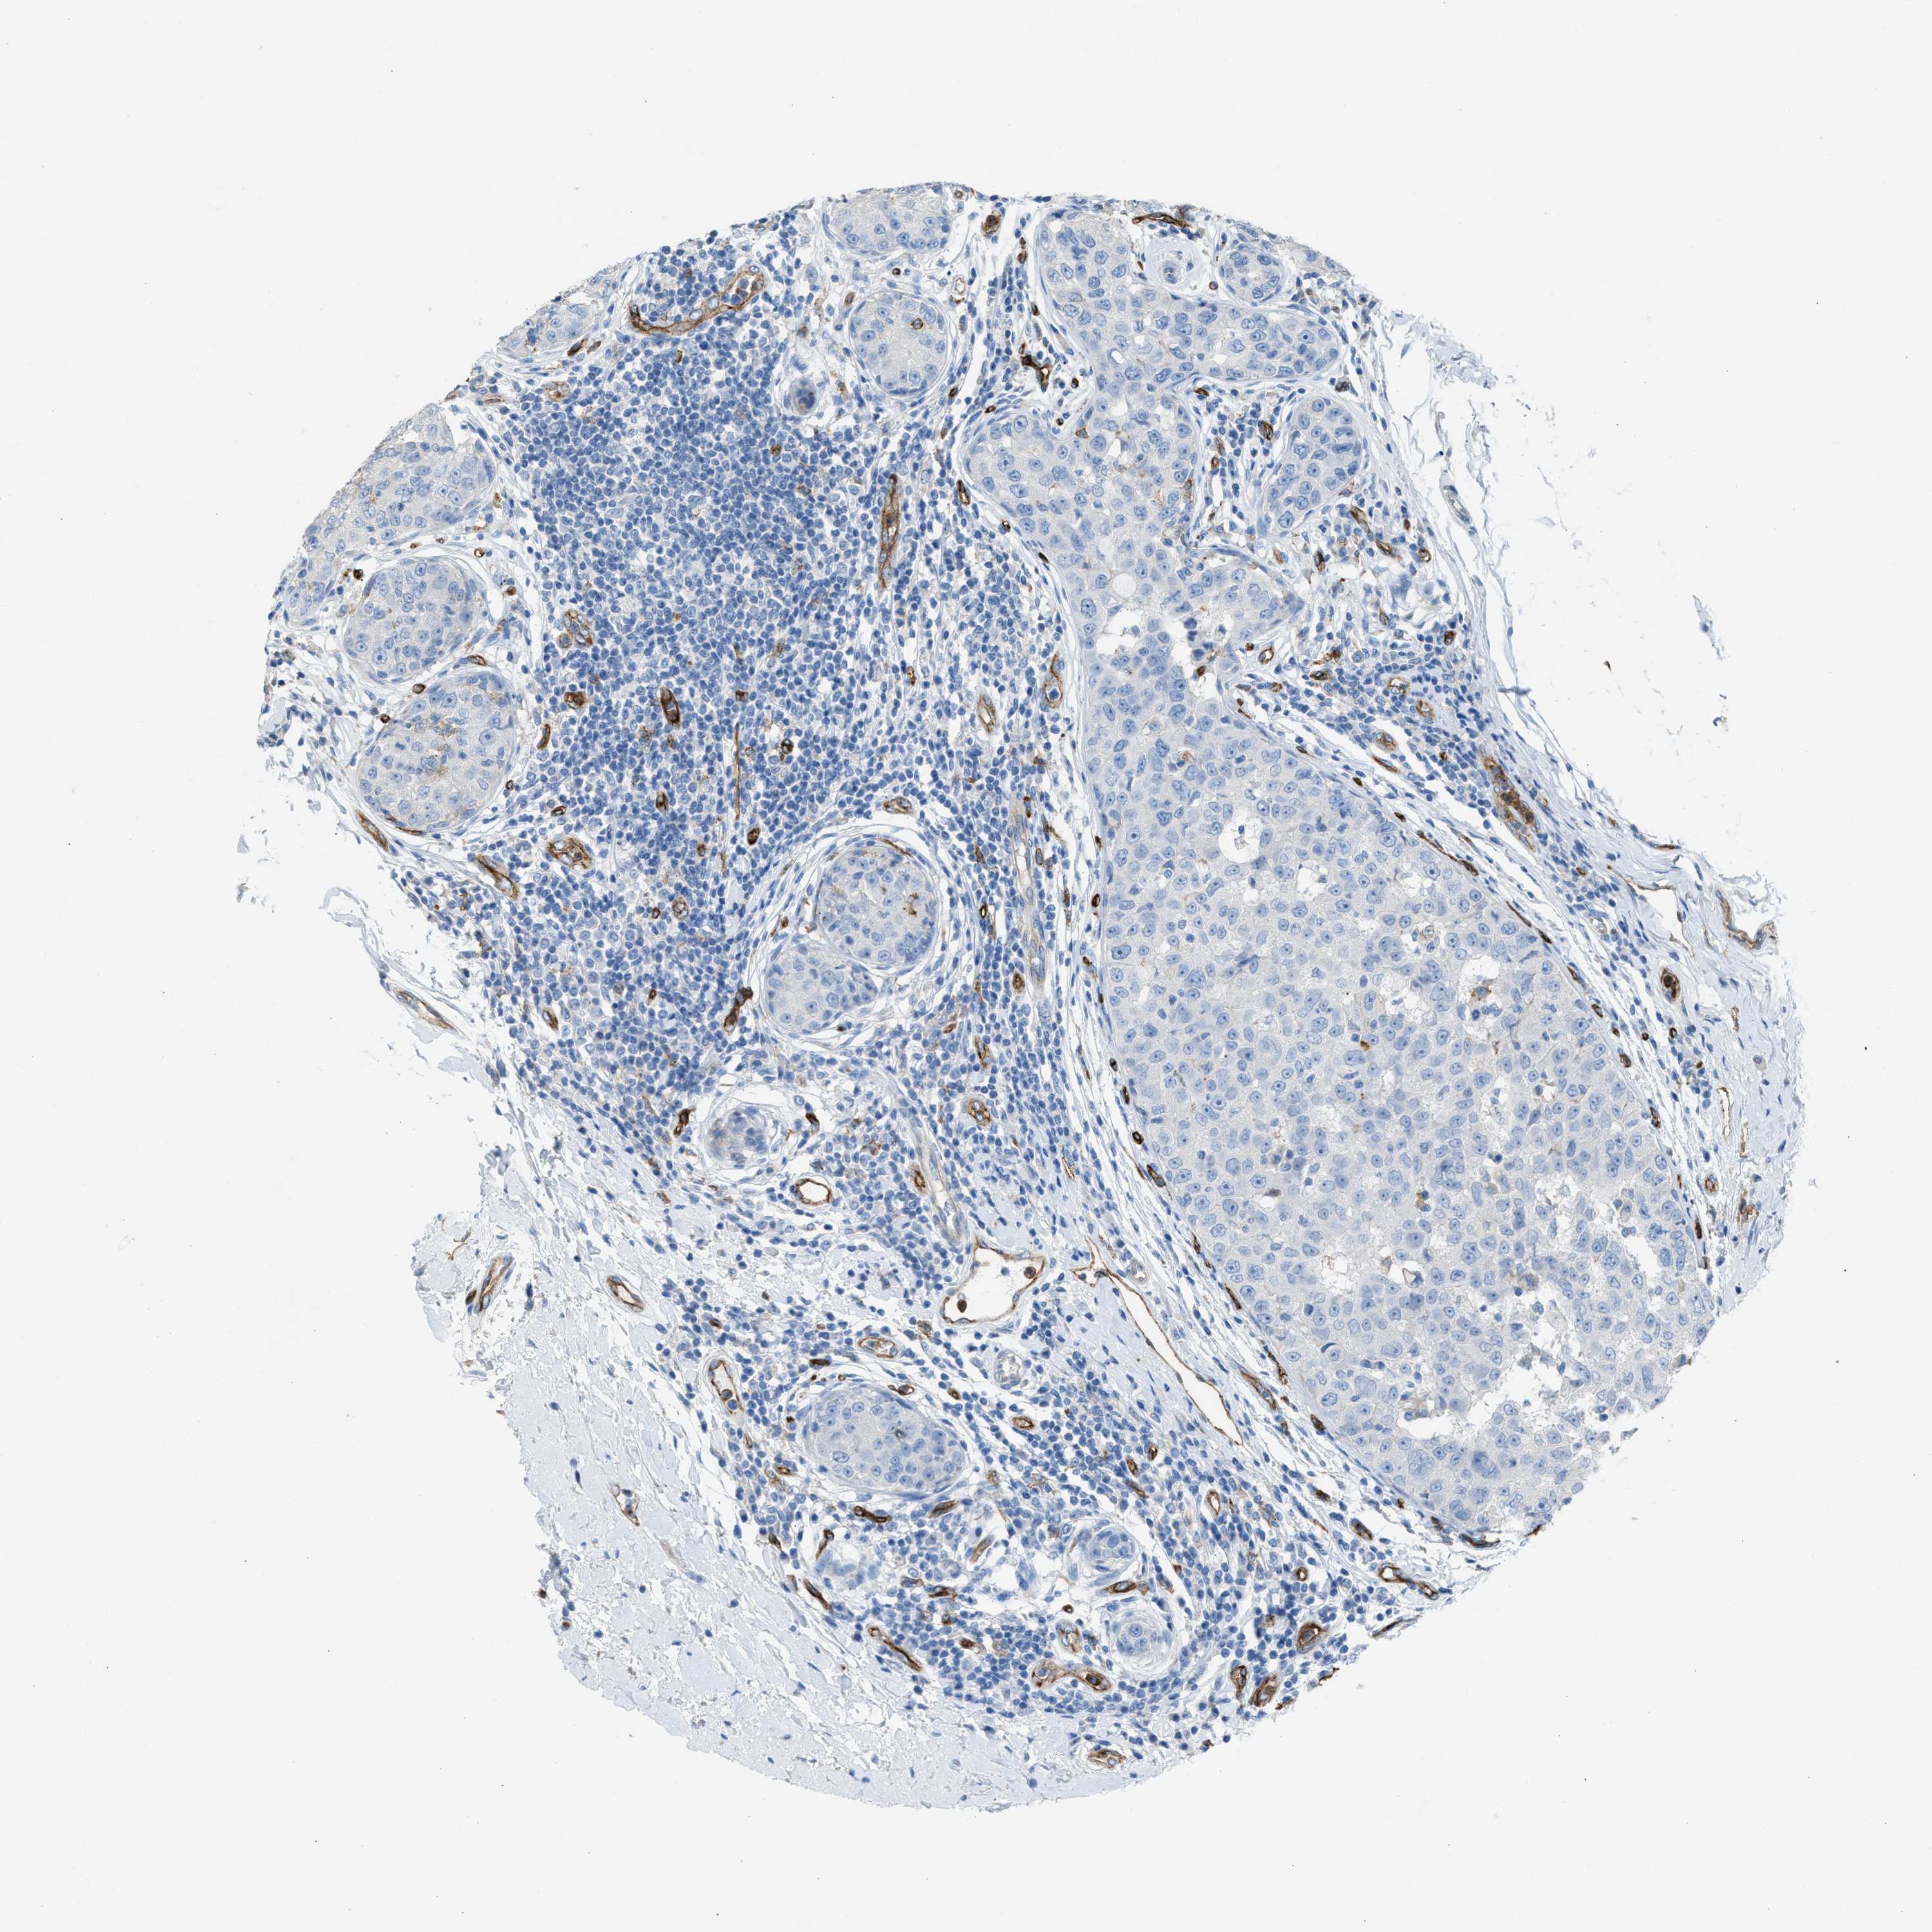

CANCER BREAST CANCER Show tissue menu

BRCA TCGA BRCA VALIDATION PROTEIN EXPRESSION